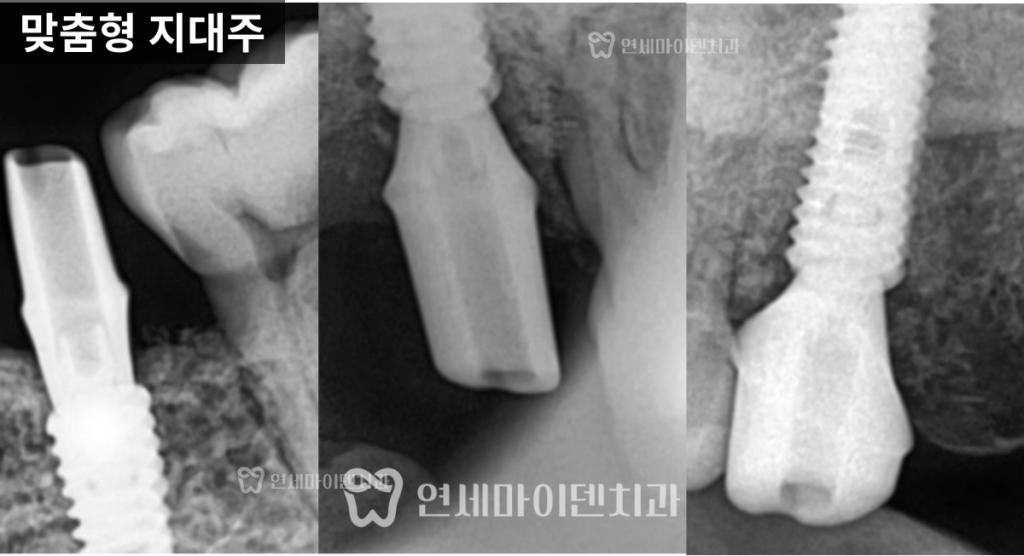

✔ 2. 보철 설계 – 맞춤형 지대주

기성 지대주를 사용하는지,

맞춤형 지대주를 사용하는지에 따라

보철의 각도와 형태가 달라집니다.맞춤형 지대주는

주변 치아와의 관계를 고려해

해부학적으로 자연스러운 형태를

만들 수 있습니다.이 부분에서

가격 차이가 발생합니다.

이번 케이스는

4년이 지난 현재까지✔ 임플란트 안정적 유지

✔ 주변 치아 뼈 레벨 유지

✔ 정기 관리 지속임플란트의 수명은